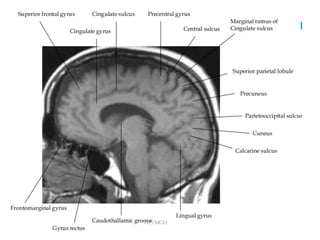

-Sagi<al	T1	image-	Parallel	to	the	corpus	callosum,	the	cingulate	sulcus

(arrowheads)	as	it	approaches	the	splenium	turns	towards	the	brain	surface.

This	extension,	the	pars	marginalis	of	the	cingulate	sulcus,	lies	immediately

posterior	to	the	central	sulcus.

Y	shaped	parieto-occipital	sulcus

-Occipital lobe is divided by calcarine sulcus into

lingual and cuneus gyrus

-Supramarginal gyrus lies at end of sylvian fissure

-Angular gyrus lies ventral to supramarginal gyrus

-Medial surface of parietal lobe is precuneus which lie immediately

rostral to parieto-occipital sulcus